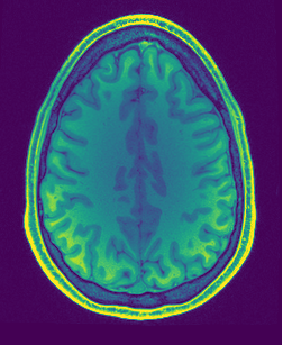

Figure 1: Reconstruction results for R = 3, with (1(a)) the fully sampled image, (b) the zero-filled image, (c) the reconstruction with no bias field estimation, (d) the joint reconstruction with bias field estimation using N4. The first three rows show reconstruction results for an HCP image, its zoomed-in version and the corresponding bias field. The next three rows show results for an in-house measured image. For visualization purposes, MR images are clipped to [0, 1.2] and bias fields, to [0.5, 1.8].

The quantitative improvement is also supported by the visual inspection of the images given in Figure 1. From the HCP image, one can observe that the level of artifacts is reduced with the proposed method. This becomes more evident in the zoomed-in images. The red arrow points to a part of the image where the proposed method can reconstruct the structures faithfully, whereas the baseline method struggles. Aliasing artifacts are globally suppressed better with the joint reconstruction method. Similarly, for the in-house measured image, the grey matter structure that the red arrow points to is not reconstructed in the baseline method, whereas it again appears with the proposed method.